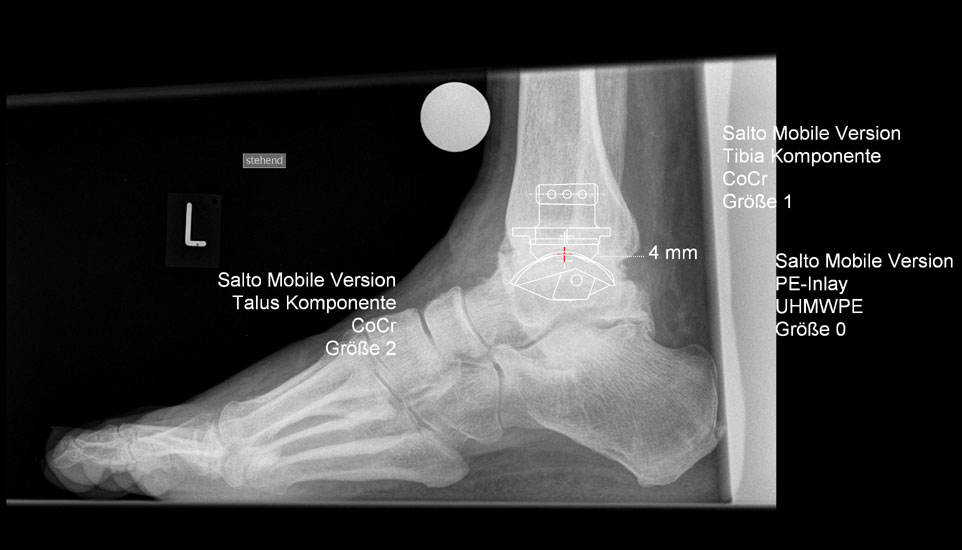

• Prothesenplanung anhand von Röntgenschablonen (Abb. 1 und 2).